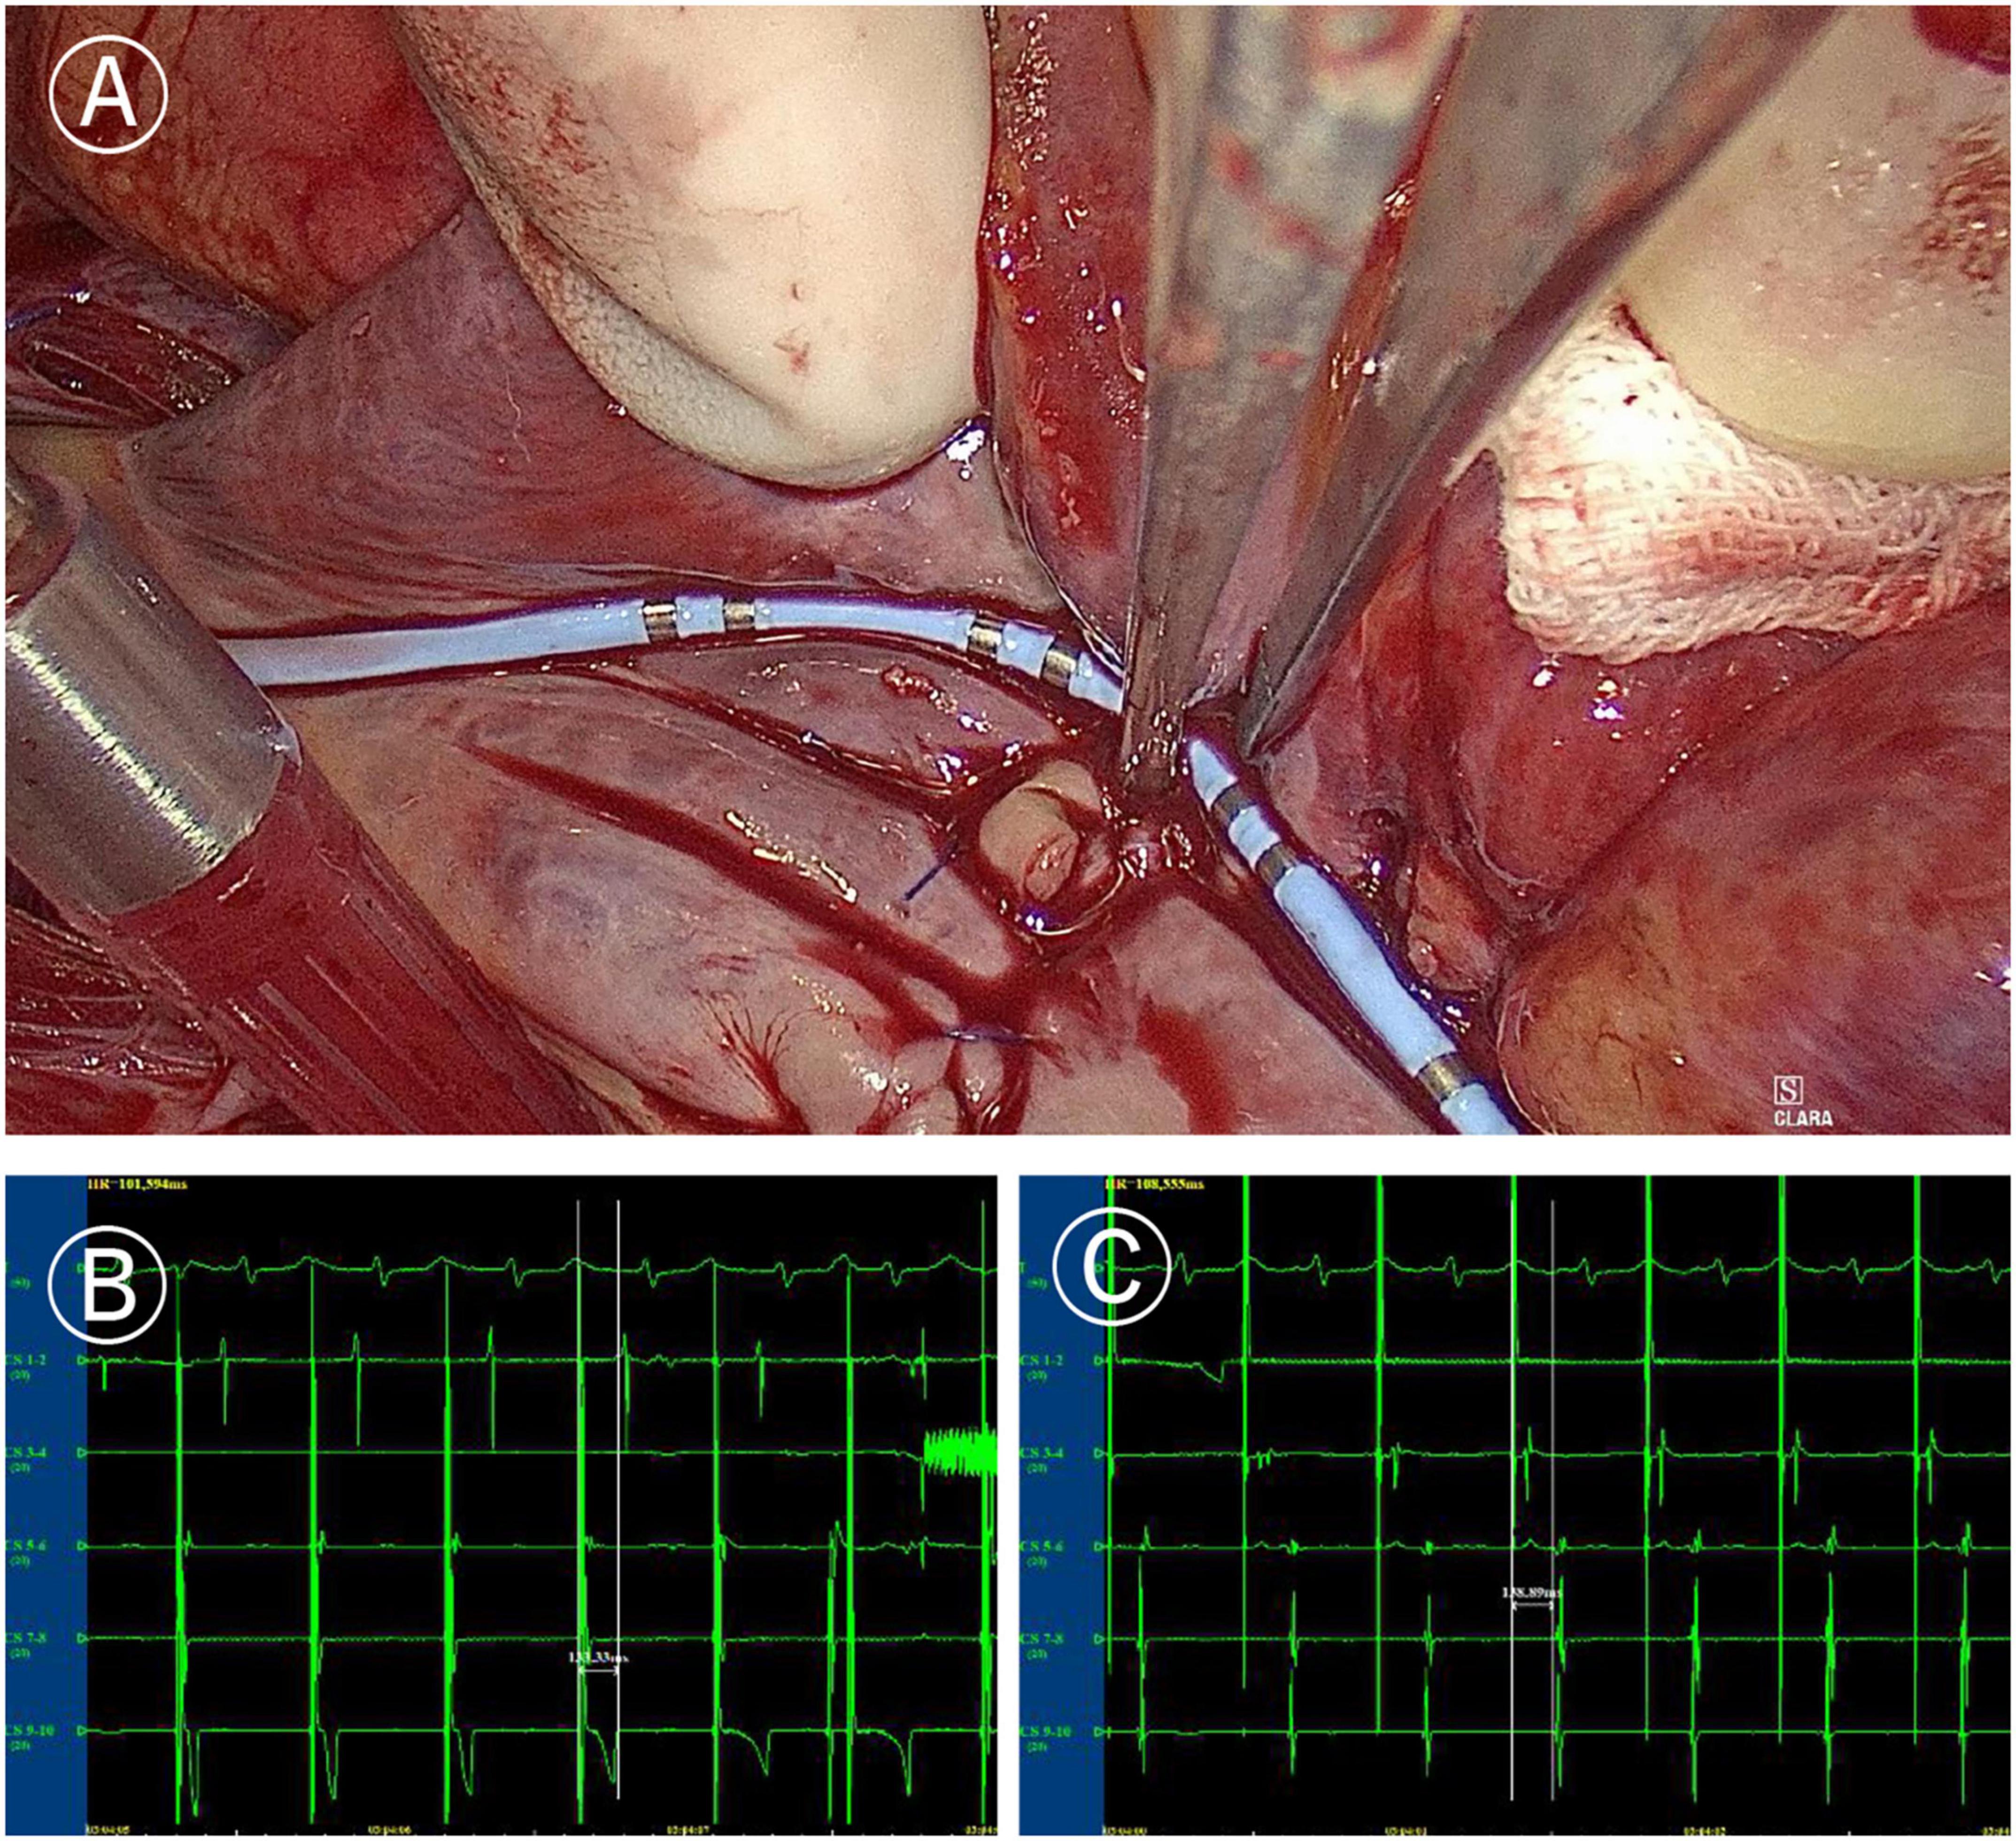

In the Electrophysio-Maze group, all patients underwent AF induction before and after the Cox-Maze IV procedure (Figure 1). The induction was performed with cannulization but without cardiopulmonary bypass, making the conditions consistent as much as possible. AF was induced in 88.1% (37/42) of all patients before Cox-Maze IV and was induced in 14.3% (6/42) of all patients after the Cox-Maze IV procedure. The bidirectional electrical isolation of the mitral annular isthmus ablation line (Figure 2), “box” ablation lines (Figure 3), and tricuspid annular ablation line (Figure 4) was successfully mapped in each patient. The rate of incomplete bidirectional electrical isolation of “box” ablation lines immediately after Cox-Maze IV was zero (the rate of complete bidirectional conduction block of “box” ablation lines immediately after Cox-Maze IV was 100%), and the rate of incomplete bidirectional electrical isolation of mitral isthmus ablation lines or tricuspid annulus ablation lines was 23.8% (10/42), wherein the rate of incomplete bidirectional electrical isolation of both mitral isthmus and tricuspid annulus ablation line was 7.14% (3/42), the rate of incomplete bi-directional electrical isolation of single mitral isthmus ablation line was 7.14% (3/42), and the rate of incomplete bidirectional electrical isolation of single tricuspid annulus ablation line was 9.52% (4/42). In two cases of incomplete bidirectional electrical isolation in single tricuspid annulus ablation line, complementary ablation was performed, and then electrophysiological mapping was performed again to ensure that the subsequent electrophysiological mapping confirmed the final complete bidirectional electrical isolation. The final incomplete bidirectional electrical isolation rate of mitral isthmus or tricuspid annulus ablation line was 19.0% (8/42). The incomplete bidirectional electrical isolation rate of ablation lines was correlated with AF inducibility immediately after Cox-Maze IV procedure but not with AF inducibility before Cox-Maze IV (Table 3).

Figure 4. Mapping of tricuspid valve annular ablation line. (A) Coronary sinus catheter mapping of tricuspid valve annular ablation line. (B) Distal polar in free side wall of the right atrium (CS1-2) delay during proximal polar near the anterior atrial sulcus (CS9-10) pacing of coronary sinus catheter (more than 120 ms). (C) Proximal delay during distal pacing of coronary sinus catheter (more than 120 ms).